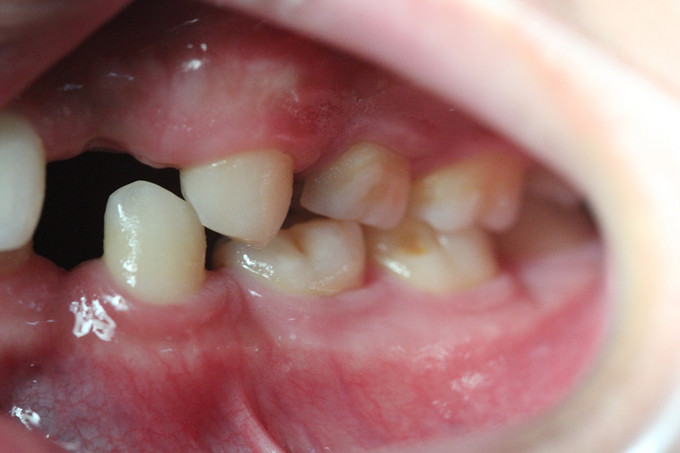

男 年龄16岁 右上恒牙2、3、4、5缺失,乳牙2、3、4、5滞留。 右下恒牙5缺失,乳牙5滞留。 左上恒牙2、3、4、5缺失,乳牙2、3、5滞留。 左下恒牙2、4、5缺失,乳牙2、5滞留。 诊断:恒牙先天缺失 治疗计划:a.乳牙治疗 b.唇系带手术 c.正畸治疗 d.种植体修复 现已经a、b两项治疗完成;因正畸难度较大,需要专家会诊共同完成!正畸治疗后再行种植修复。